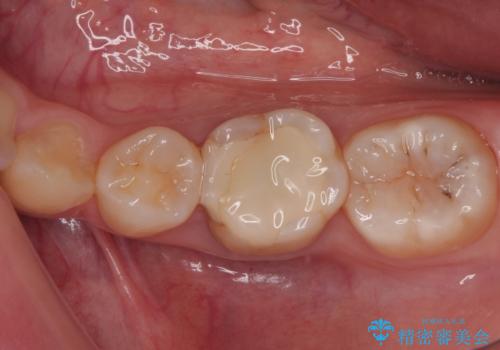

奥歯も著しく茶色に変色していたため、同様にオールセラミッククラウンにて補綴治療を行うこととしました。

明るく自然な口元になりました。